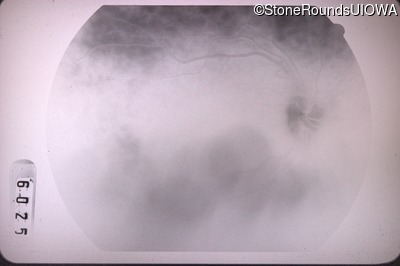

Fluorescein Angiography - Right - 20/40 -2

Exemplar